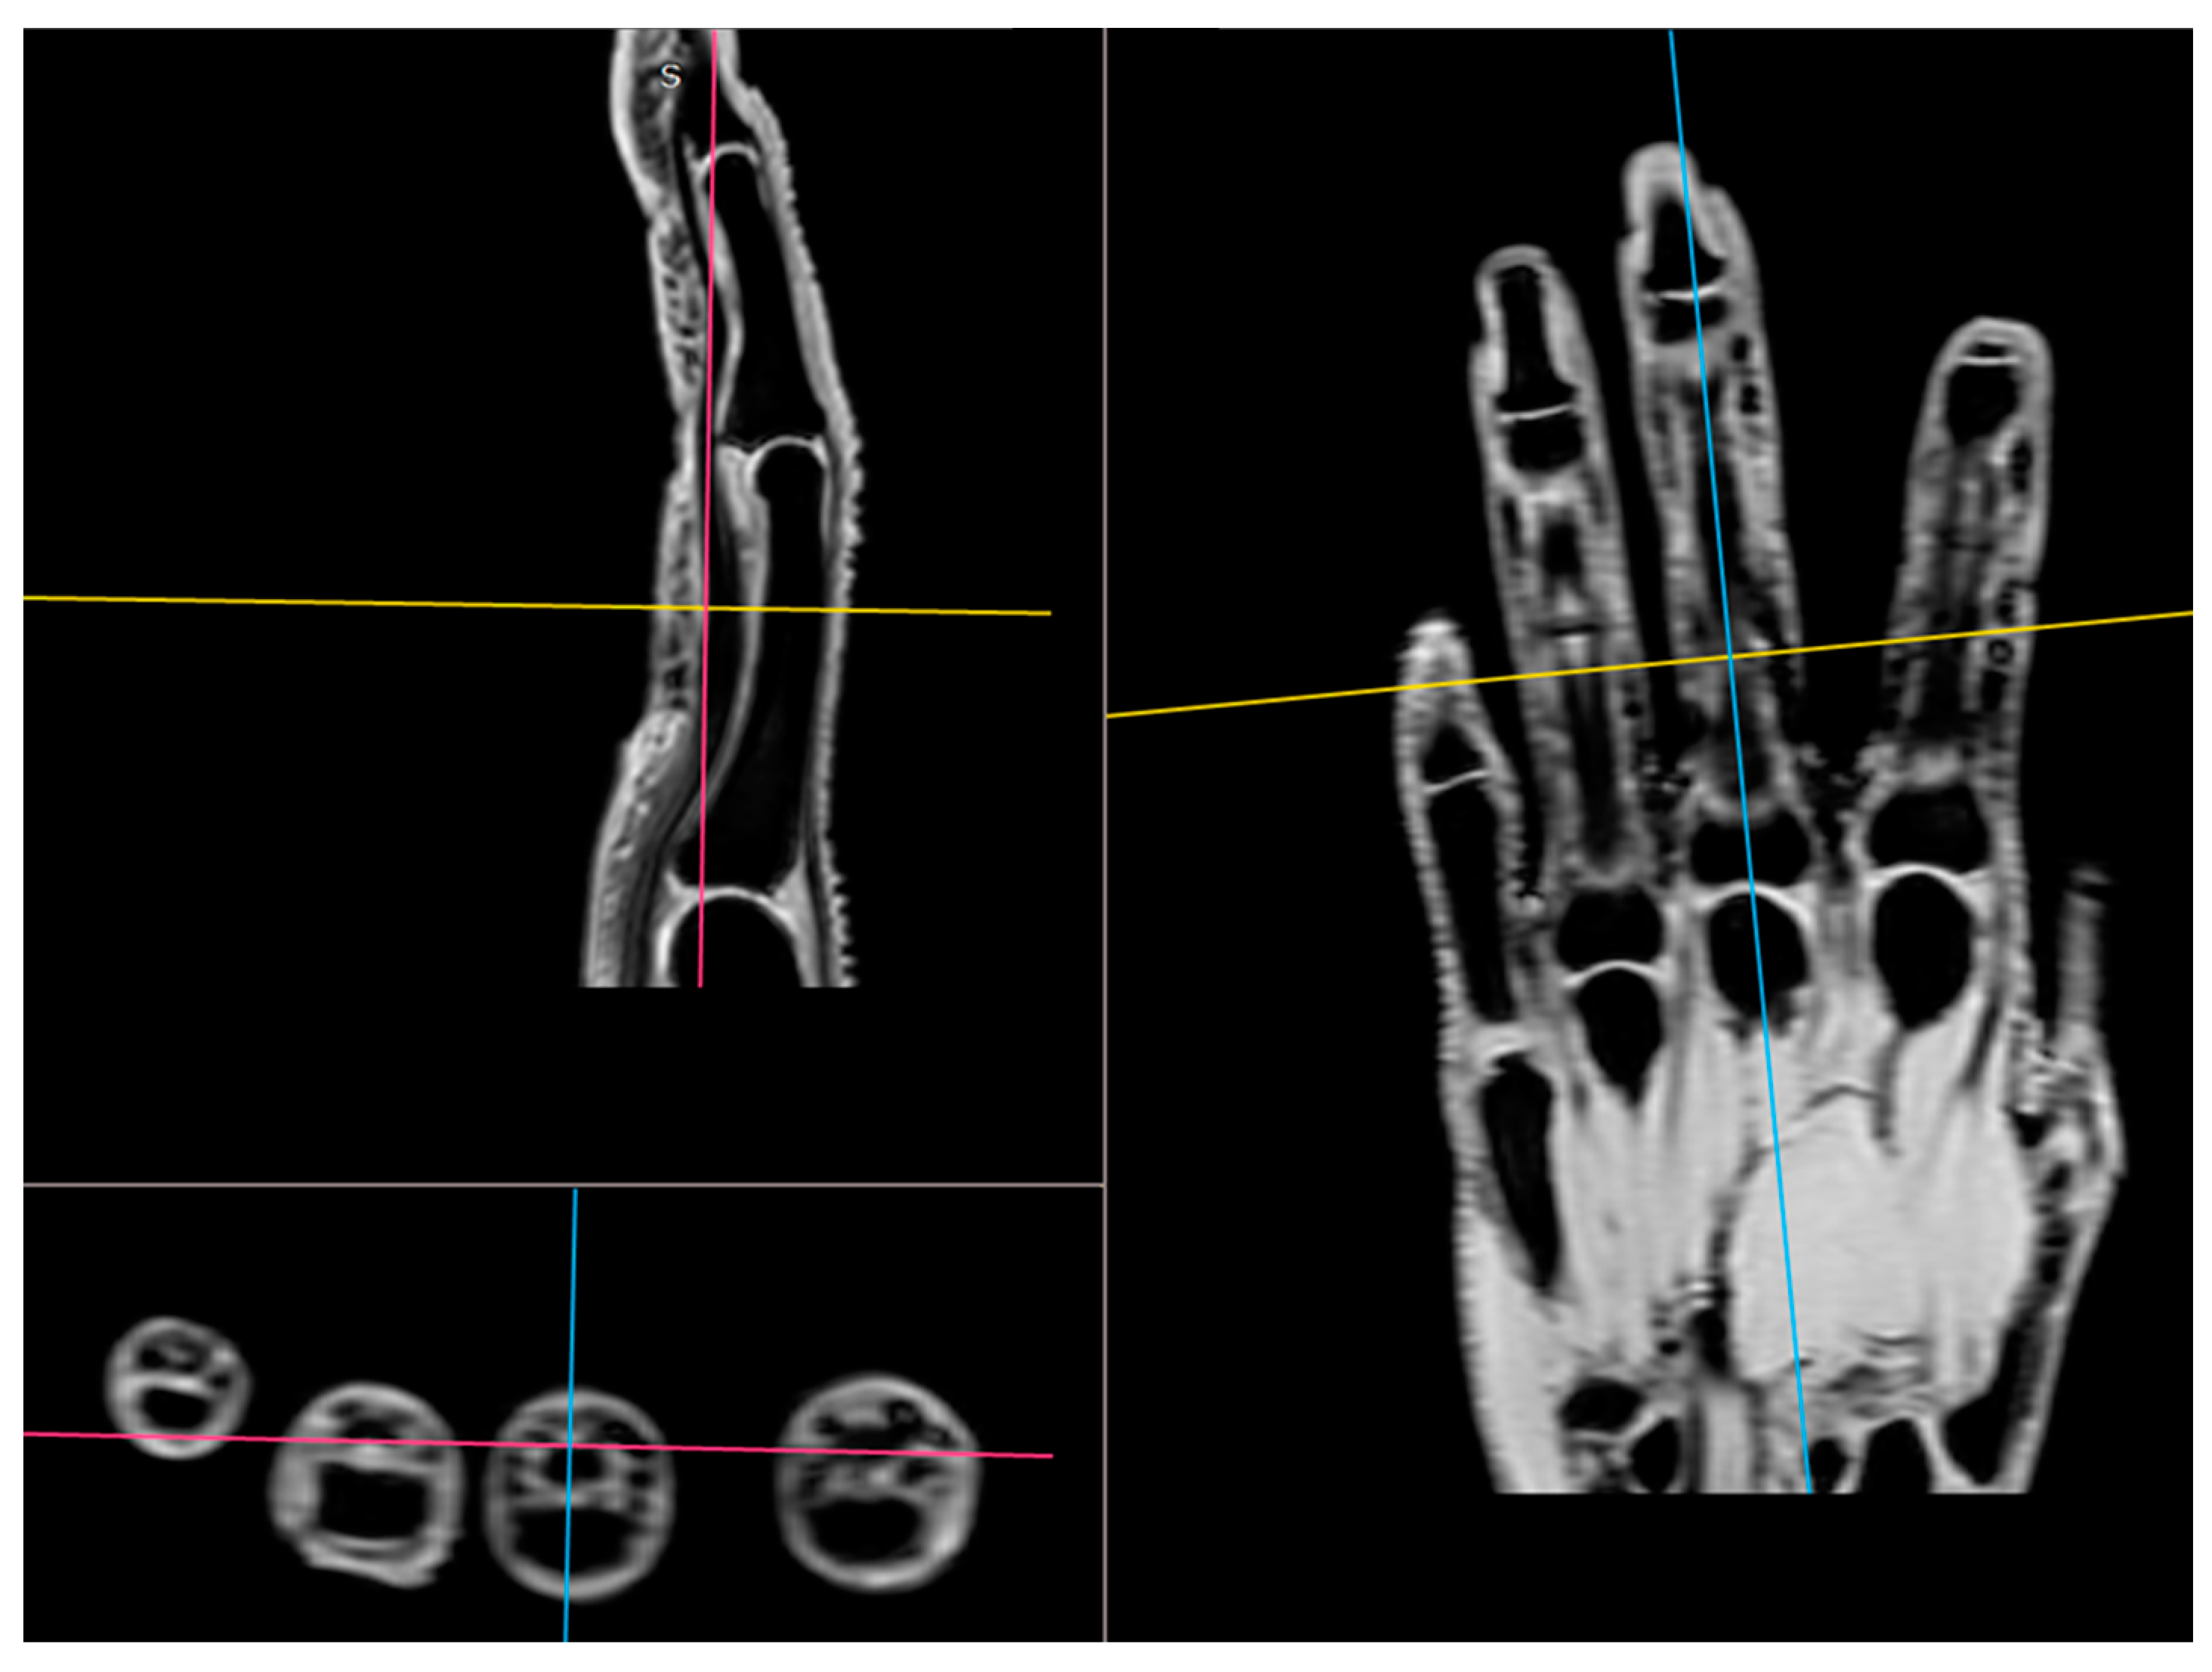

2.4. Magnetic Resonance Imaging